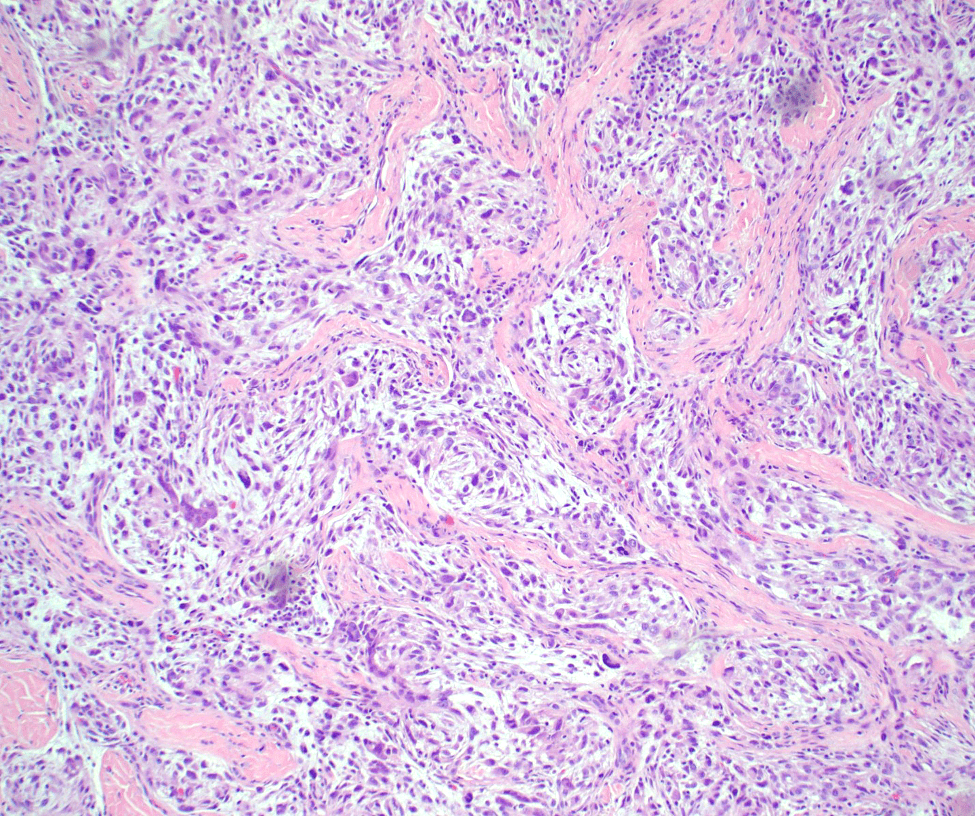

Microscopic findings

- Spindled to epithelioid cells arranged in whorls and fascicles against a myxoid background

- The cells are present in the dermis

- Dense bundles of collagen separate the cells into nodules

- Variable nuclear atypia

Figure 2: H&E, 100x- Individual cells are spindle-to-epithelioid against a myxoid stroma